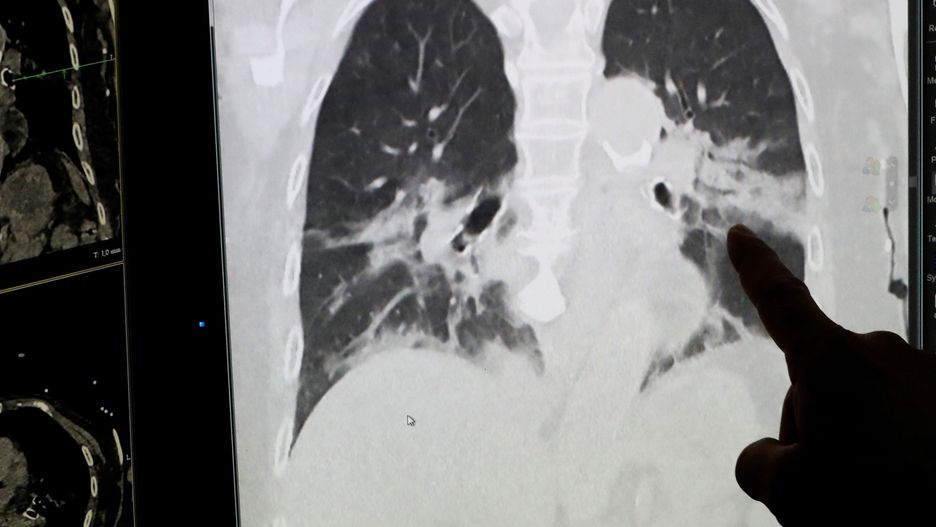

Lekarze z Kliniki Uniwersyteckiej w Innsbrucku (Austria) przebadali sześć osób wyleczonych z COVID-19. Mimo że wszyscy przeszli chorobę łagodnie, to zauważono u nich poważne i nieodwracalne uszkodzenia płuc.

Koronawirus stanowi poważne zagrożenie dla płuc.

Lekarze z Kliniki Uniwersyteckiej w Innsbrucku (Austria) przebadali sześciu austriackich nurków. Wszyscy byli zakażeni koronawirusem, ale mieli łagodne objawy i przebywali w domowej kwarantannie. 5-6 tygodni temu uznano ich za wyleczonych.

Badania wykazały jednak, że choroba COVID-19 wywołała u nich trwałe uszkodzenia płuc. Austriacy, którzy wcześniej byli uznawani za zdrowych, nie będą mogli wrócić do nurkowania.

Uszkodzenia płuc są nieodwracalne. To szokujące, nie rozumiemy, co się tutaj dzieje - powiedział w rozmowie z APA lekarz z Kliniki Uniwersyteckiej w Innsbrucku Frank Hartig.

Koronawirus niszczy przede wszystkim płuca. To, jak wpływa na ten organ, pokazali m.in. lekarze z USA, którzy udostępnili film obrazujący uszkodzenia płuc w wyniku COVID-19 u 59-letniego pacjenta. Mężczyzna wcześniej poważnie nie chorował. Nie palił papierosów i prowadził zdrowy tryb życia. Wirus w krótkim czasie zaatakował oba płuca mężczyzny.